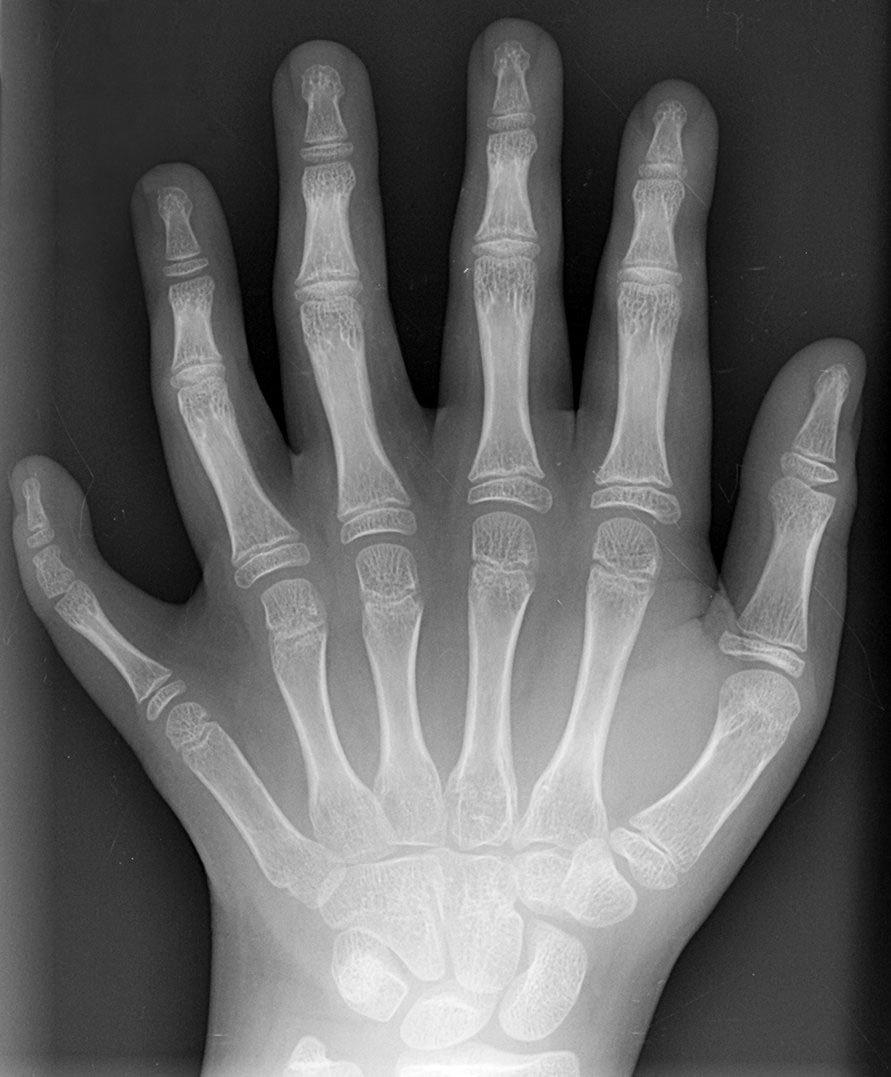

Getting into one of the most prestigious schools in the world looks pretty common compared to a shark attack (shutterstock). - Being born with extra fingers or toes (Polydactyly; 1 in 500)